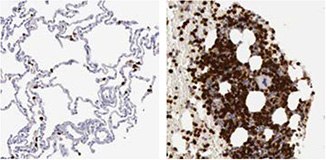

The IHC analysis using the Anti-RBM3 antibody HPA003624 showed a weak expression pattern in normal breast tissue, but a stratified pattern in breast cancer tissue (Figure 1). Researchers further investigated the expression in larger breast cancer cohorts and the expression of RBM3 was shown to be associated with a prolonged survival5.

Figure 1. Immunohistochemical analysis using the Anti-RBM3 antibody (HPA003624) shows weak expression in normal breast tissue (A) and differential expression, varying from weak to strong in tumor breast samples (B, C).